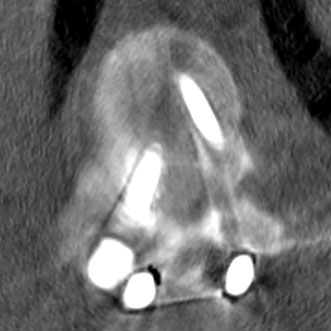

Traumatic Physeal Arrests at the Wrist

Current Concept Review

Laura Bellaire, Carley Vuillermin, Suzanne Steinman, Walter Truong, Donald Bae, Doug Wallace, Christine Ho